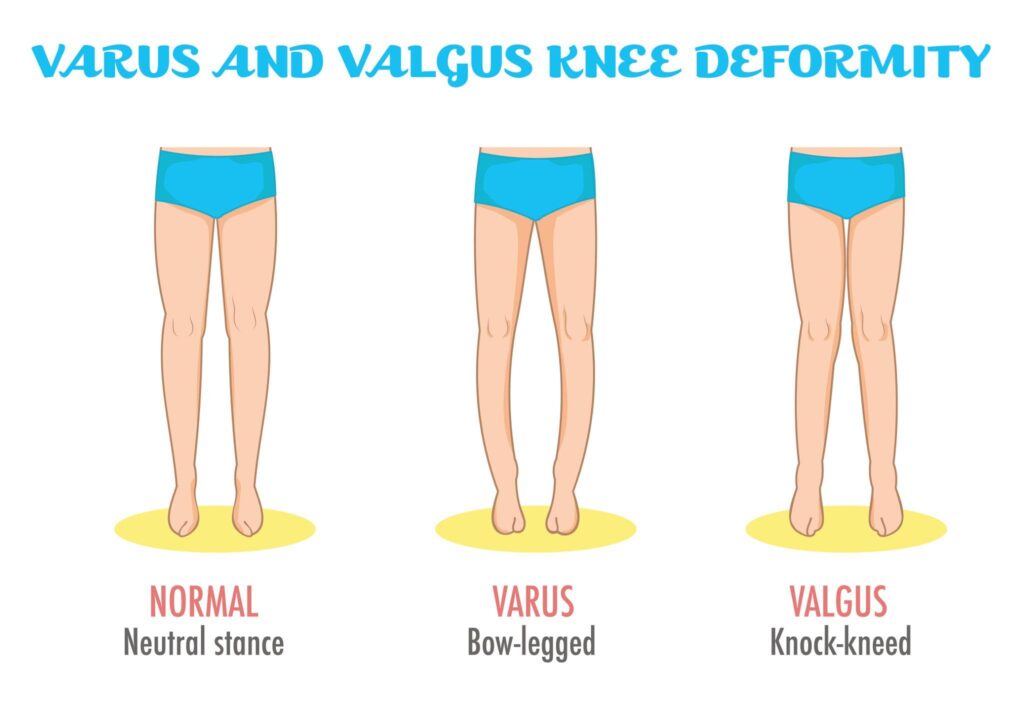

Bowing of the legs is a common knee alignment condition medically known as genu varum, or varus deformity. In this condition, the legs curve outward at the knees, giving a bow-shaped appearance. It occurs when the tibia (shin bone) turns inward instead of aligning properly with the femur (thigh bone), causing the knees to move away from the body’s midline.

The alignment between the femur and tibia is called tibiofemoral alignment. Ideally, this alignment forms a straight 180-degree angle. When the angle deviates, even slightly, it can go unnoticed for years before symptoms appear.